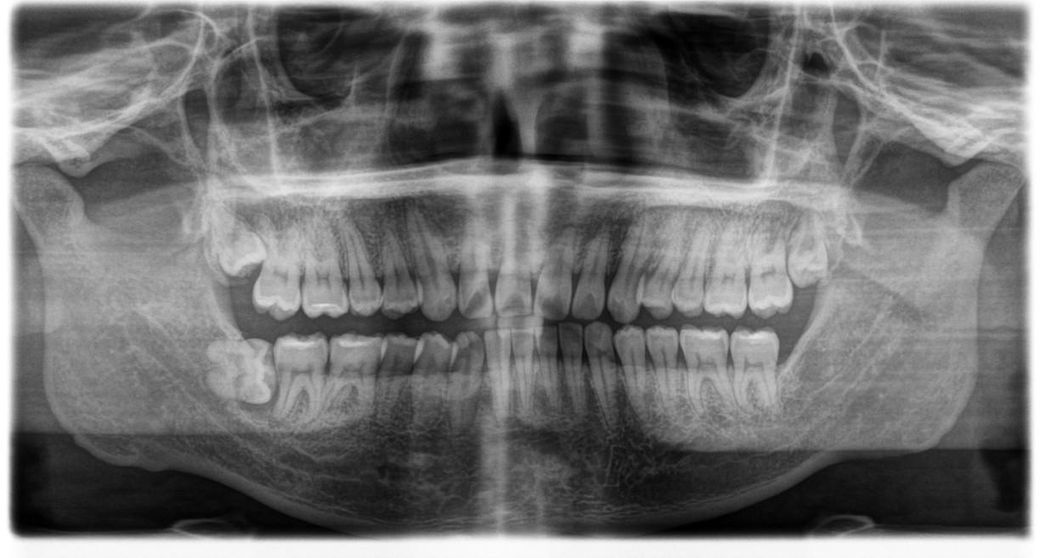

• 1번 째 사진

저정도면 47번 근심치근측 뼈가 치아를 잡아주기 때문에 동요도가 심하진 않을거고, 사랑니 빼고 기다리면 뼈는 차오릅니다.

굳이 뼈이식을 할 필요가 있어보이진 않습니다

여기서 치조제 보존술은 치조골 이식과는 별개 이야기입니다. 치조제 보존술은 해당사항 없습니다.

사진에 보이는사랑니를 발치하고나서 골이식을 하는건 크게 의미가 없고 만약 문제가 생겨서 앞치아를 발치를 하고 임플란트를 한다면 그땐 골이식이 필요해 보입니다.